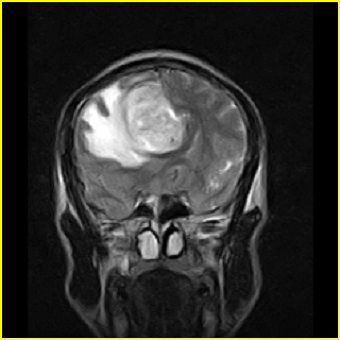

男,45岁,头部剧烈疼痛伴呕吐5天。

右侧额叶见较大的类圆形长t1信号环绕等t1环影,长t2信号环绕短等t2环,周围见明显水肿占位征,中线结构左移,男,45岁,头部剧烈疼痛伴呕吐5天。

右侧额叶,见一占位病灶,t1像病灶、水肿长t1;其间为短t1环行信号。t2像病灶、水肿长t2,其间为短t2环行信号。占位效应明显,中线左移,右测脑室受压闭塞。结合患者发病较急。首先考虑:右侧额叶脑脓肿形成。鉴别:1、转移瘤,多发多见2、胶质瘤。建议增强

t1加权肿瘤呈低信号,肿瘤壁呈等信号.t2 加权时肿瘤呈高信号,肿瘤壁呈等信号.

考虑1脑脓肿.2恶性胶质瘤.